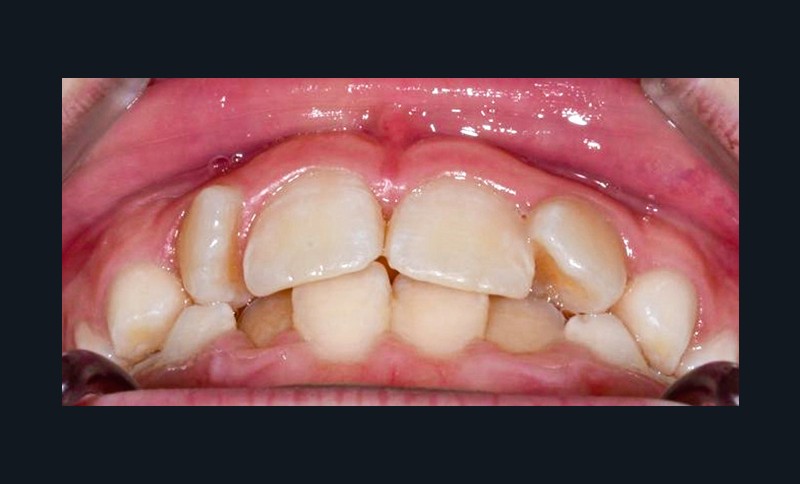

L’appareil est déposé après la mise en place de contentions collées de 12 à 22 et de 33 à 43 avec le port nocturne d’une plaque de Hawley à l’arcade maxillaire. Le temps de traitement actif a été de 41 mois.